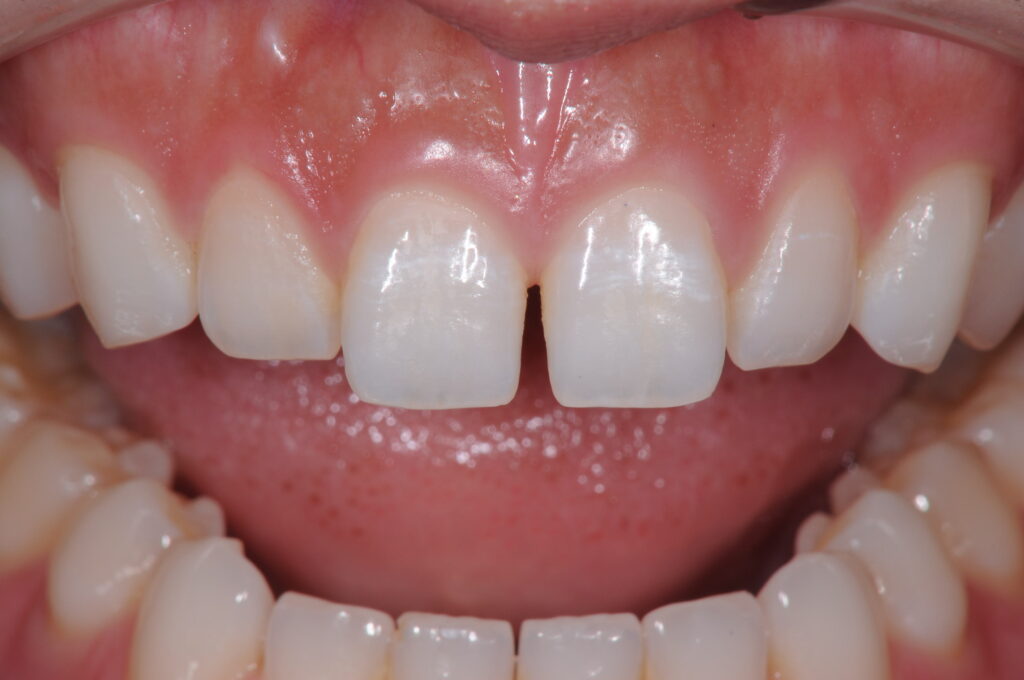

歯の隙間を埋めたい(30代)ダイレクトボンディング

年齢 30歳 性別 女性 初診日 2019年9月 主訴 審美障害 治療内容 ダイレクトボンディング 治療期間 2日 治療費用 66000円 ×2本 治療経過 歯の隙間を埋めたいという主訴で来院された。 空隙を埋める方法としては矯正治療と修復治療が選択できるが、今回の…